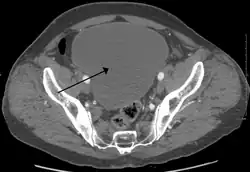

Urinary retention with greatly enlarged bladder as seen by CT scan.